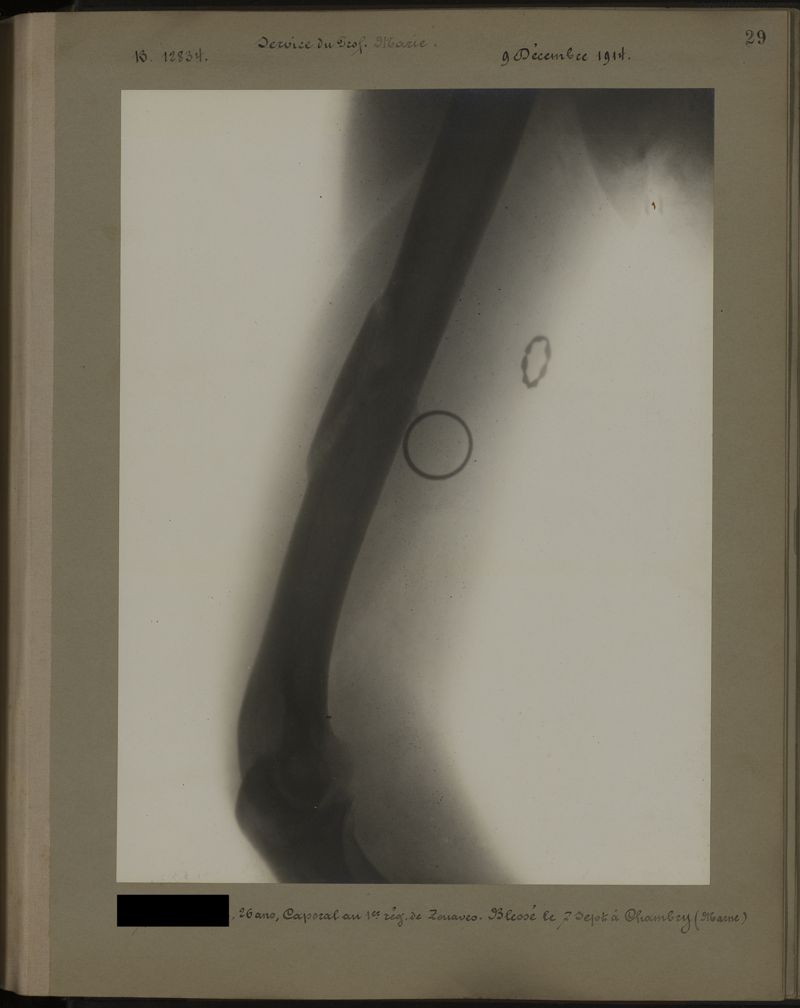

Deux albums de radiographies de la Première Guerre mondiale. Collection du laboratoire central de radiographie de la Salpêtrière. Deuxième album.

1915.